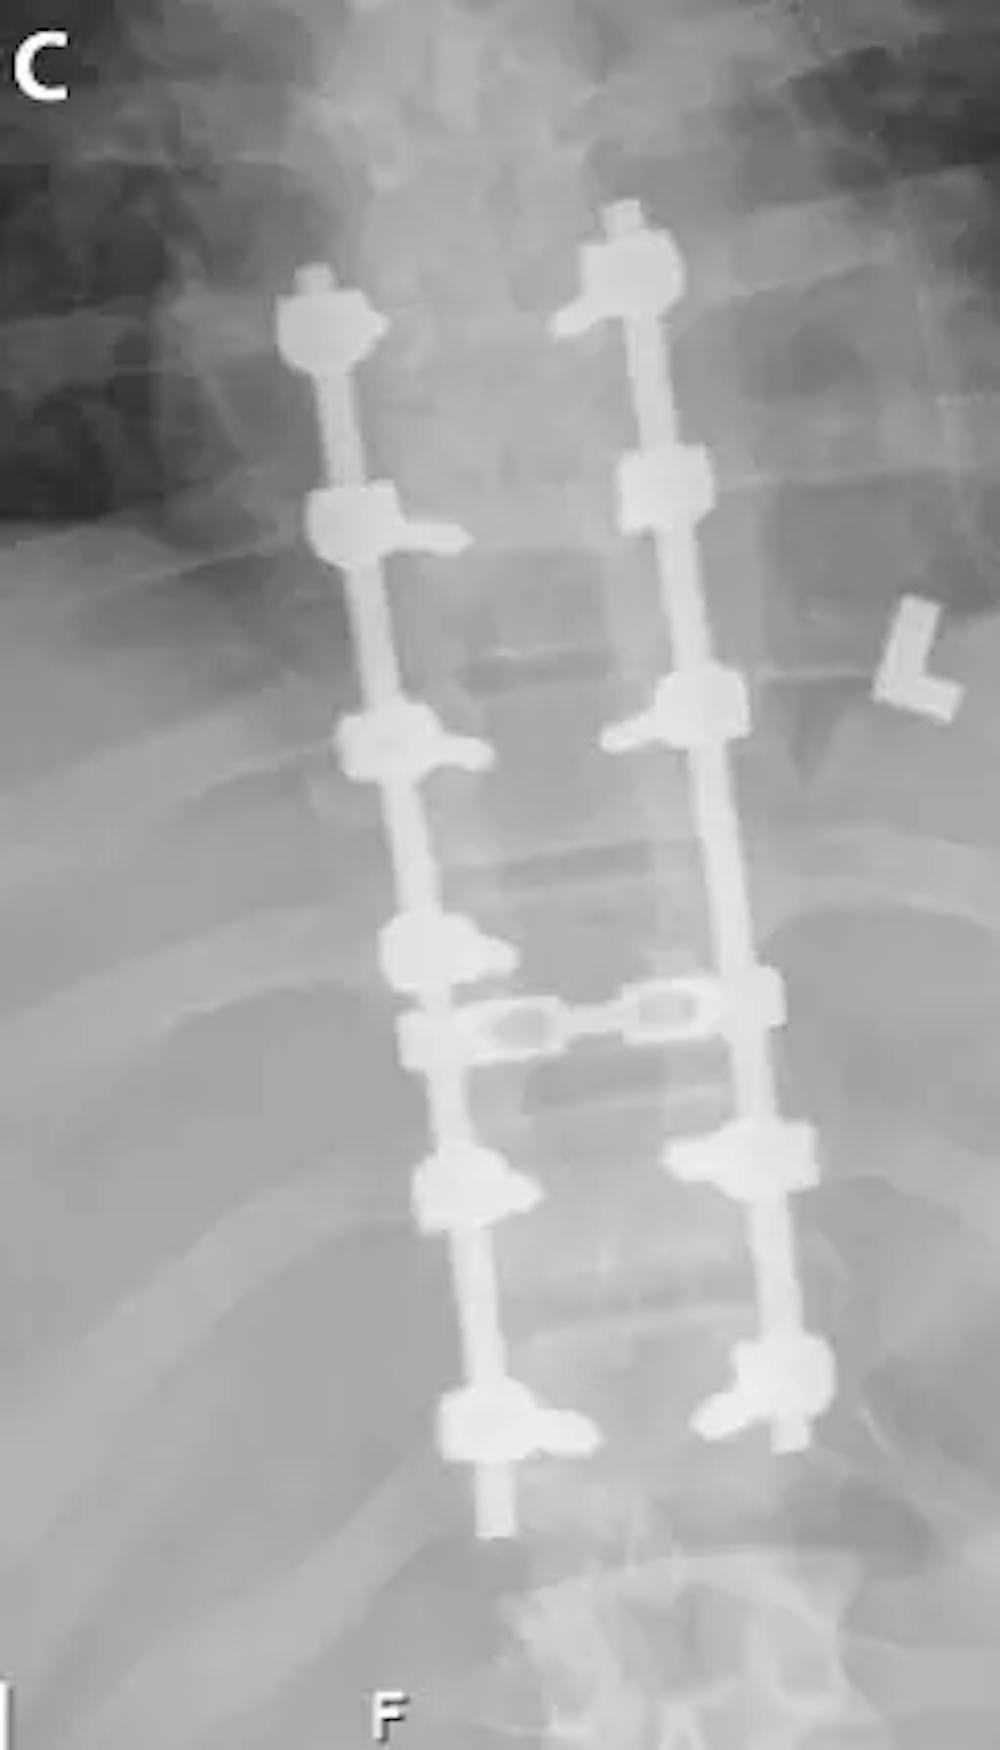

C) پوسٹ آپریٹو اے پی ایکس رے چھاتی کے پیڈیکل پیچ اور سلاخوں کا مظاہرہ کرتا ہے۔